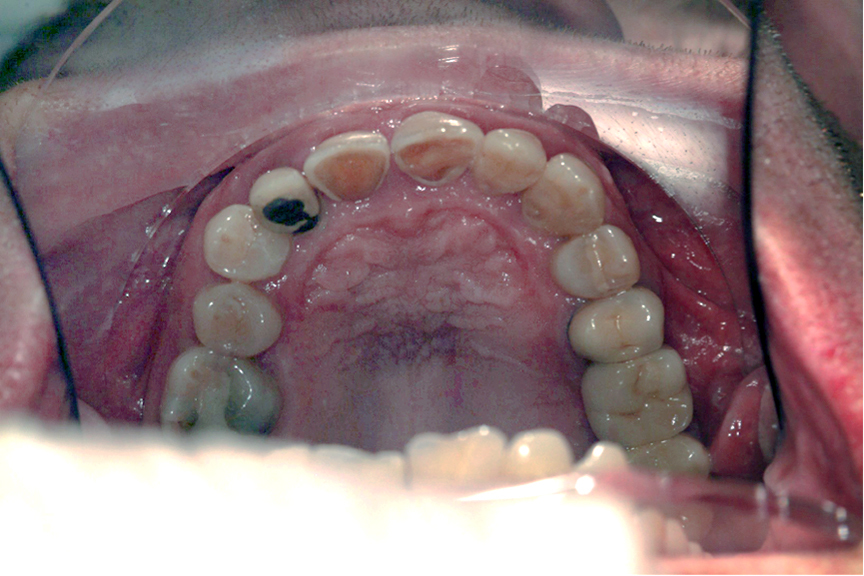

The patient presented with a class I molar and canine relationship on the right side, and a class II molar and canine relationship on the left side, a deep bite, and lingually inclined lower and upper incisors. In addition, the upper left second premolar was missing, several teeth had filling or restoration and the lower incisors were severely worn.

To allow a prosthetic rehabilitation that was able to ensure an aesthetic result respectful of the basic principles of a correct occlusion, we decided to use Nuvola aligners to level the curve of Spee, open the bite, and improve the axial inclination of upper and lower incisors. To achieve a proper alignment in the mandibular arch, the extraction of a lower incisor was performed. Clear aligners were the best choice for this case, since they permit very selective orthodontic movements, the presence of heavily filled teeth is not an issue and the oral hygiene is not impaired.

After orthodontic alignment, the case was finalised with metal-ceramic prosthetic crowns from UR6 to UL3 and from LL4 to LR4. As can be seen from the photographs, the aesthetic result achieved with Nuvola aligners was further improved with the prosthesis, confirming that a synergic approach like the one showed is successful in providing the best treatment option for the patient.